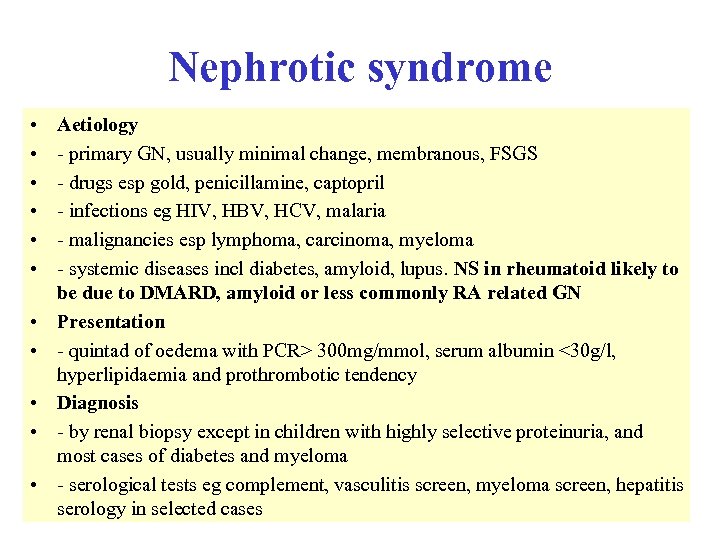

Nephrotic syndrome • • • Aetiology - primary GN, usually minimal change, membranous, FSGS - drugs esp gold, penicillamine, captopril - infections eg HIV, HBV, HCV, malaria - malignancies esp lymphoma, carcinoma, myeloma - systemic diseases incl diabetes, amyloid, lupus. NS in rheumatoid likely to be due to DMARD, amyloid or less commonly RA related GN Presentation - quintad of oedema with PCR> 300 mg/mmol, serum albumin <30 g/l, hyperlipidaemia and prothrombotic tendency Diagnosis - by renal biopsy except in children with highly selective proteinuria, and most cases of diabetes and myeloma - serological tests eg complement, vasculitis screen, myeloma screen, hepatitis serology in selected cases

Nephrotic syndrome • • • Aetiology - primary GN, usually minimal change, membranous, FSGS - drugs esp gold, penicillamine, captopril - infections eg HIV, HBV, HCV, malaria - malignancies esp lymphoma, carcinoma, myeloma - systemic diseases incl diabetes, amyloid, lupus. NS in rheumatoid likely to be due to DMARD, amyloid or less commonly RA related GN Presentation - quintad of oedema with PCR> 300 mg/mmol, serum albumin <30 g/l, hyperlipidaemia and prothrombotic tendency Diagnosis - by renal biopsy except in children with highly selective proteinuria, and most cases of diabetes and myeloma - serological tests eg complement, vasculitis screen, myeloma screen, hepatitis serology in selected cases